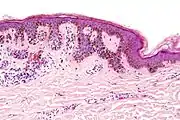

Low magnification

Micrograph of a dysplastic nevus showing the characteristic rete ridge bridging, shouldering, and lamellar fibrosis. H&E stain.